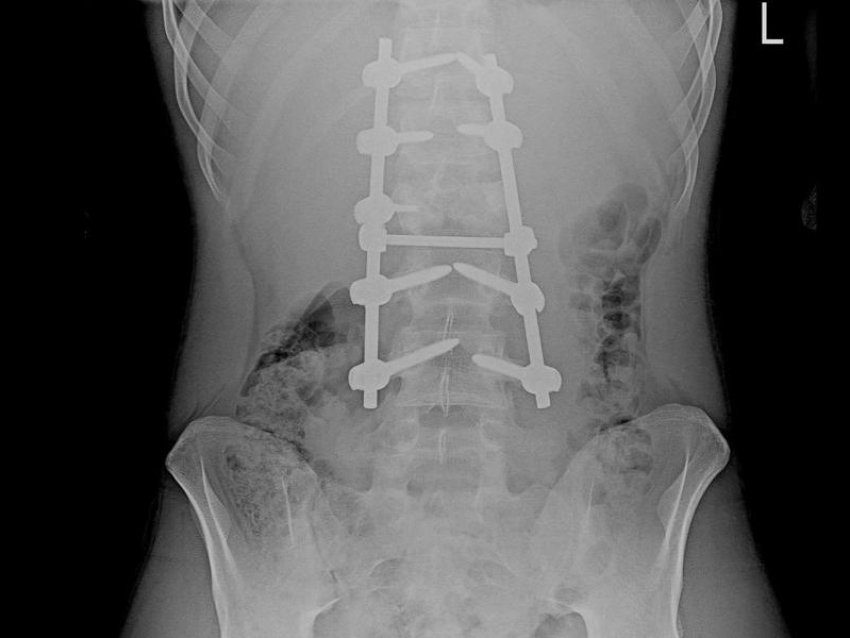

В БСМП №1 подростку провели сложнейшую операцию, выполнив стабилизацию пяти позвонков с помощью специальной металлической конструкции из титановых винтов и стержней, удалили задние и передние структуры позвонка из заднебокового доступа.